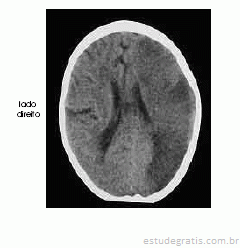

Um homem com 67 anos de idade, lavrador, deu entrada no pronto-socorro após ter sido encontrado, em sua casa, no chão e com dificuldade para falar e deambular. O paciente morava sozinho e os parentes não sabiam informar sobre uso de medicações ou patologias pregressas. Na avaliação, o neurologista identificou afasia mista, hemianopsia homônima direita e hemiparesia direita de predomínio braquifacial. Apesar de apresentar sonolência, o paciente ficava alerta ao chamado. A pressão arterial era de 180 mmHg × 90 mmHg. Foram solicitados exames complementares e de imagem, dos quais uma das imagens é reproduzida abaixo.

É possível relacionar o quadro clínico em questão a doença vascular em território da artéria cerebral média esquerda.